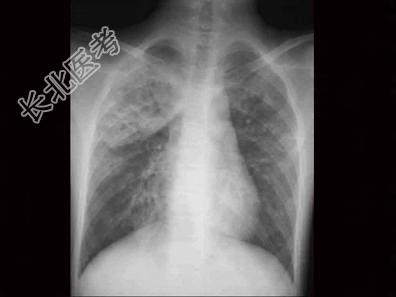

- 单项选择题患儿11个月,突发高热4天, 烦躁,咳嗽频繁, 呻吟,发病前3天有皮肤破损及感染史, 肺部有散在中、细湿啰音,胸部X线可见斑点状结节阴影, 见图,血象白细胞总数增高, 核左移,该患儿最可能诊断为  (    )

A、金黄色葡萄球菌性肺炎